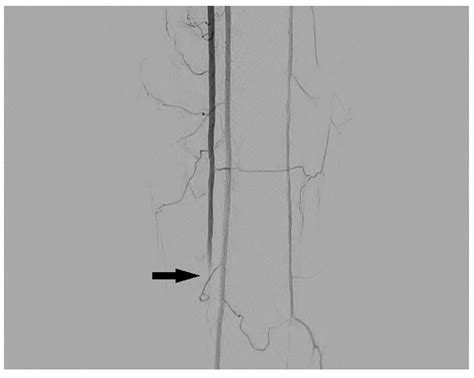

At its core, Digital Subtraction Angiography is a fluoroscopic technique that uses a computer-aided process to subtract the background image from a subsequent image taken after the injection of a contrast agent. The process begins with a "mask" image, which captures the anatomy of the target area without any contrast. Once the radiopaque contrast dye is injected into the bloodstream, a second set of images is captured. The computer then mathematically subtracts the mask from the contrast-filled images, leaving only the opacified vessels visible on the screen.

This process effectively removes visual "noise," allowing interventional radiologists to see even the smallest branches of an artery. Because of its superior contrast sensitivity and spatial resolution, it remains the preferred method for assessing conditions like aneurysms, stenosis, and arteriovenous malformations.